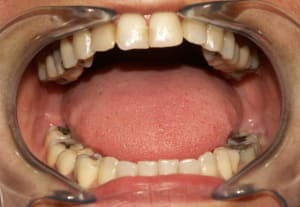

Cas_3_b_izilst.jpg

Voir le message contenant cette image